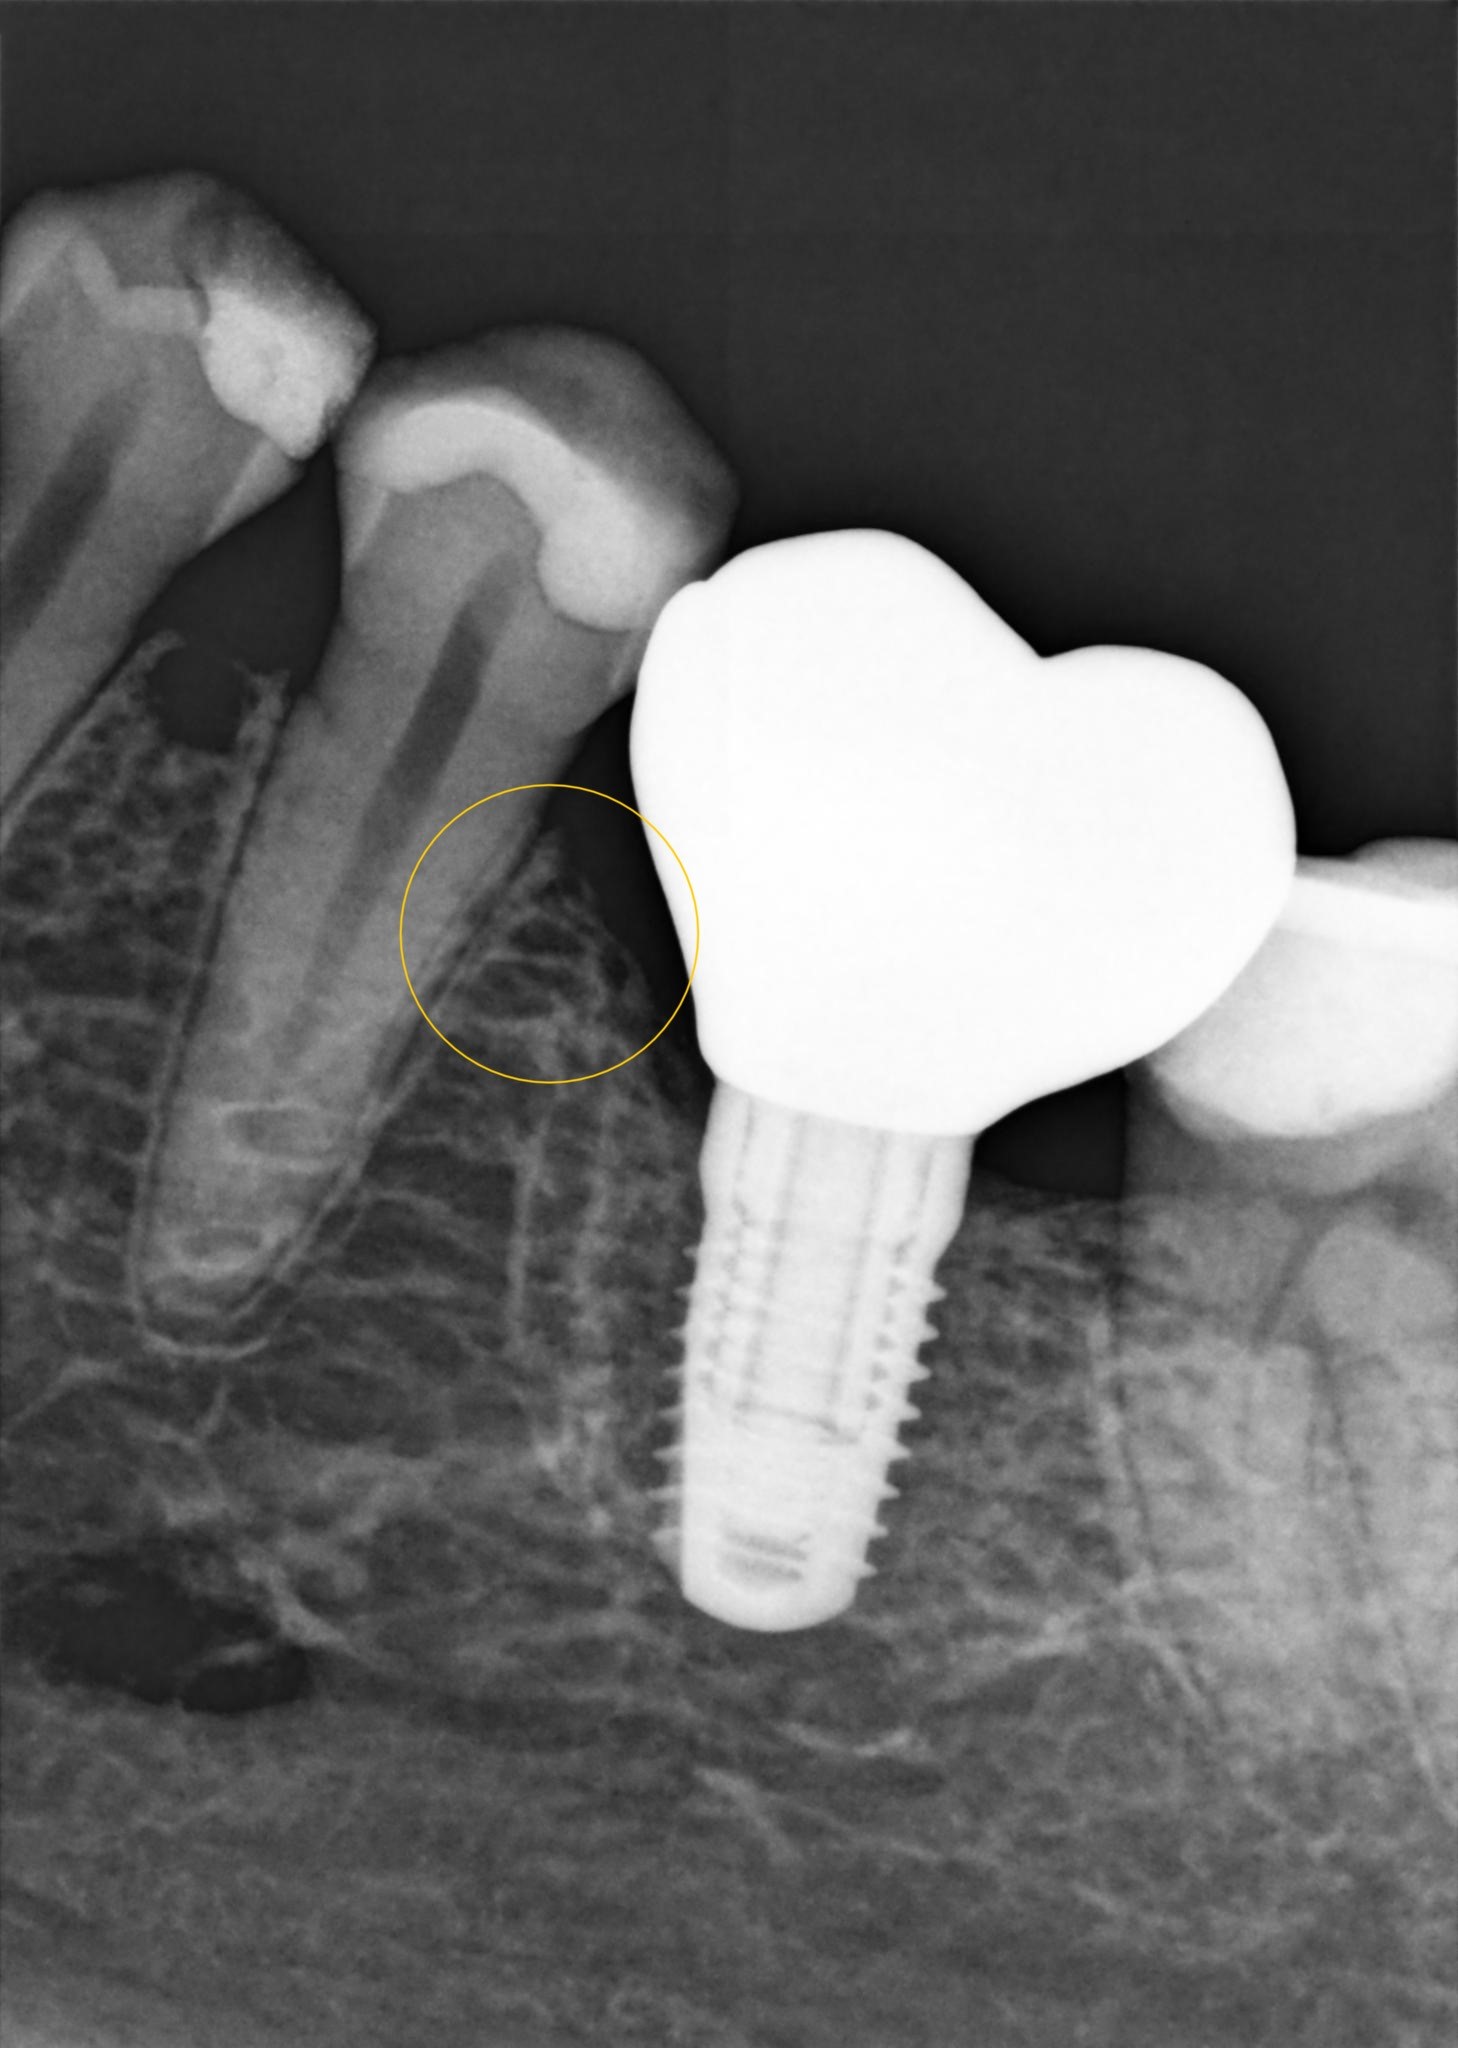

Das ist das aktuellste Röntgenbild.